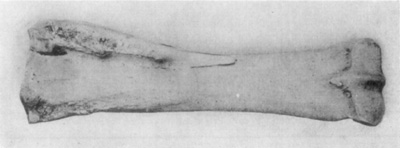

Simple Fracture is a condition where the continuity of the bone has been broken without serious destruction of the soft structures adjacent, and where no opening has been made to the surface of the flesh. Such fractures do not reduce the bone to fragments. Long bones are frequently subjected to simple fracture, while short thick bones, such as the second phalanx, may suffer multiple or comminuted fractures.

A fracture is transverse when the bone is broken at a right angle from its long axis. Such breaks when simple, are the least trouble to care for because there is little likelihood that the broken ends of bone will become so displaced that they will not remain in apposition. Simple transverse fracture of the metacarpus, for instance, constitutes a favorable case for treatment if other conditions are favorable.

Oblique fractures, as may be surmised, are solutions of continuity of bone in such manner that the fissure crosses the long axis of a bone at an acute or obtuse angle. These fractures are prone to injure the soft structures adjacent, and are frequently compound, as well. Moreover, because of the fact that the apposing pieces of bone are beveled, the broken ends of bone are likely to pass one another in such a way as to shorten the distance between the extremities of the injured member. Contraction of muscles also tends to exert traction upon a bone so fractured, resulting in a lateral approximation of the diaphysis and thus preventing union because the broken surfaces are not in proper contact.

Fractures are longitudinal when the fissure is parallel with the long axis of the bone. This variety of break is not infrequent in the first phalanx; and a vertical fracture of the second phalanx is also said to be longitudinal, however, there is little difference (if any, in some subjects) between the vertical and transverse diameters of this particular bone.